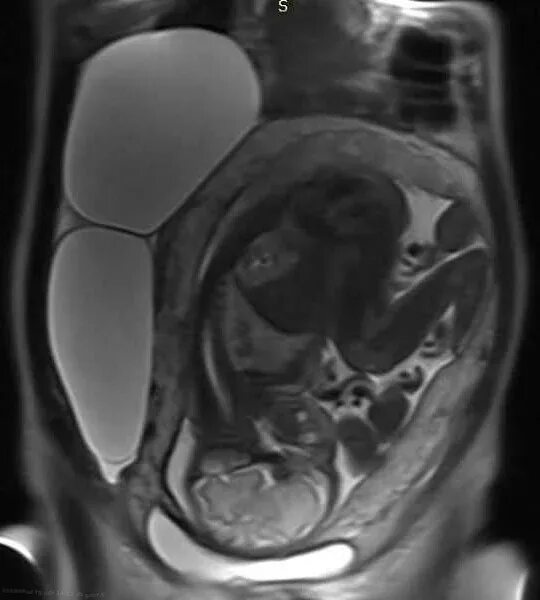

Мрт беременной